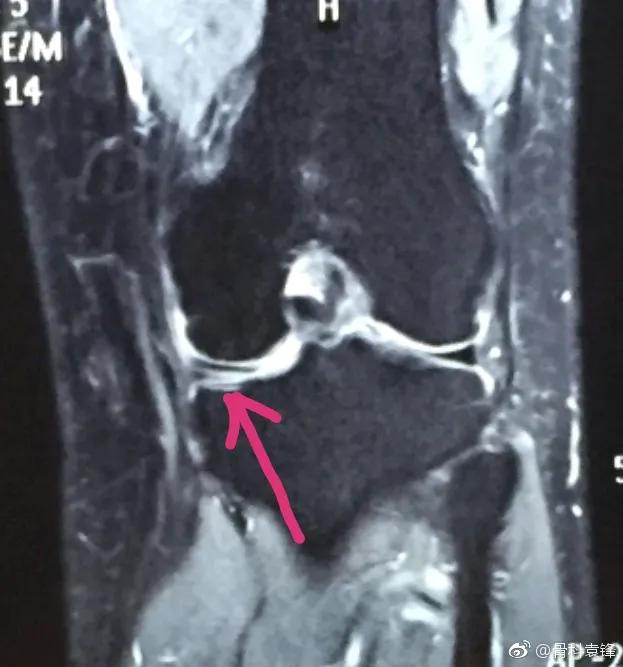

1、对于急性损伤,查体有明显或轻微症状,磁共振显示3度撕裂的信号,建议尽快关节镜手术治疗。

2、对于急性损伤,查体有明显症状或轻微症状,磁共振显示1-2度信号,建议先行保守治疗,可佩戴支具一月以上,一月后开始适当负重活动,以及伸屈活动度的锻炼,三个月内避免运动。如三月后恢复,则无需手术。如三月后症状持续,可关节镜手术。

3、对于无明显诱因或慢性劳损引起的疼痛,查体有明显或轻微症状,磁共振显示3度信号,和查体一致。可尽快行关节镜手术治疗。磁共振显示1-2度信号,症状持续3个月以上,可行关节镜手术。

4、对于无任何症状或不适,查体无症状,磁共振显示随便几度信号,均应保守治疗。症状和体征永远是第一位的。应休息制动,三月内避免运动。值得一提的是,有部分患者膝关节磁共振显示明显的三度。但是膝关节疼痛不明显,仅仅走路走得多有一些酸胀,我们说这些酸胀其实也是属于有症状,这种情况磁共振确的是三度撕裂的,也是要手术治疗的。